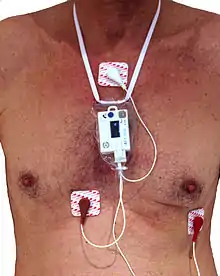

3-lead Holter monitor | |

When used to study the heart, much like standard electrocardiography, the Holter monitor records electrical signals from the heart via a series of electrodes attached to the chest. Electrodes are placed over bones to minimize artifacts from muscular activity. The number and position of electrodes varies by model, but most Holter monitors employ between three and eight. These electrodes are connected to a small piece of equipment that is attached to the patient's belt or hung around the neck, keeping a log of the heart's electrical activity throughout the recording period. A 12-lead Holter system is used when precise ECG information is required to analyse the exact origin of the abnormal signals.[5]

The size of the recorder differs depending on the manufacturer of the device. The average dimensions of today's Holter monitors are about 110x70x30 mm, but some are only 61x46x20 mm and weigh 99 g.[6]